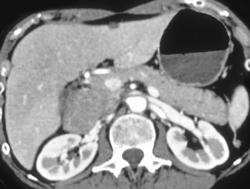

Cancer of the Pancreas Invades the Hepatic Artery